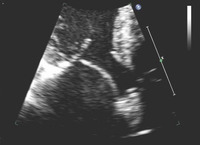

Parasternal long-axis view showing posterior mitral leaflet prolapse

From the collection of Samir Kapadia and Mehdi H. Shishehbor

See this image in context in the following section/s: